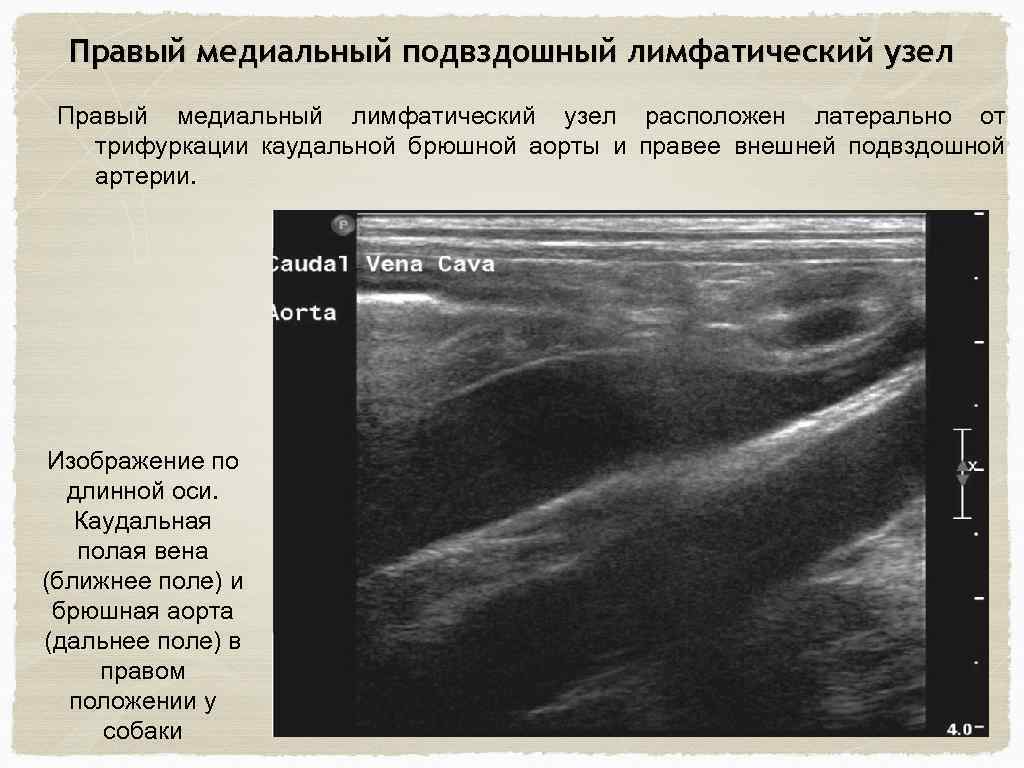

Правый медиальный подвздошный лимфатический узел Правый медиальный лимфатический узел расположен латерально от трифуркации каудальной брюшной аорты и правее внешней подвздошной артерии. Изображение по длинной оси. Каудальная полая вена (ближнее поле) и брюшная аорта (дальнее поле) в правом положении у собаки